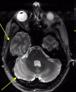

Recently FDA-approved 7 Tesla (T) MRI can provide improved signal-to-noise ratio, resolution, and image contrast when compared with standard clinical MRI scanners (usually 1.5T or 3T). However, proton imaging at higher frequencies (~300MHz) and shorter wavelength (~13cm in brain tissues) can lead to inhomogeneities in the images and potentially cause high localized radiofrequency (RF) power deposition in the tissue. The Tic-Tac-Toe (TTT) RF coil system provides improved homogeneity and reduced power deposition. It is achieved thanks to an innovative coil design and a methodology of operation. Several clinical MRI sequences have been performed and compared with commercial RF coils, demonstrating the superior performance of the Tic-Tac-Toe RF coil system. Numerous clinical studies including NIH funded studies (~2,000 subjects) are currently being conducted using this coil at the University of Pittsburgh.

b) a) c) The Tic-Tac-Toe (TTT) radiofrequency head coil for 7T MRI Fig 1: in a), the implemented 16-channel TTT transmit RF coil; in b), the computational RF coil in c), the implemented RF coil with an 32-channel receive insert Fig. 2: The B1+ (magnetic field responsible for spin excitation) field homogeneity is highly degraded at 7T MRI due to a higher operational frequency (~297MHz). The TTT presents a more homogeneous field distribution when compared with the NOVA coil (a commercial coil) [1]. Measured Tic-Tac-Toe Measured Nova coil Regions with low B Simulated Tic-Tac-Toe B + maps in the brain: TTT vs NOVA RF coils TTT coil NOVA coil TTT coil NOVA coil Image comparison with the 32-channel NOVA commercial RF coil a) b) Fig. 3: In a), Turbo spin echo (TSE) sequence using the TTT coil with resolution of 0.4x0.4x2mm. In b), the same TSE sequence acquired with the commercial NOVA coil. In c), FLAIR sequence acquired with TTT coil with resolution of 0.7x0.7x2mm. In d), the same FLAIR sequence acquired with NOVA coil. The arrows point to regions of dark spots in the NOVA coil images and compare with similar regions on the TTT coil images [1]. c) d) High-resolution susceptibility weighted images showing cortical microvessels Fig 4 SWI images acquired at 0 2x0 2x1 5mm resolution In a) an axial slice of the whole brain image acquisition In b) and c), zoomed versions of a), detailing the micro-structures a) b) c) High resolution angiography without contrast agents 380μm a) b) Fig 5: Maximum intensity projection orientation and small vessels detectability isotropic image showing whole brain isotropic acquisition In d), 0 20mm are only detectable at higher resolution

Finger tapping task: activation of Functional MRI a) Diffusion MRI and fiber tracking Post-mortem a) a) b) Fig 7 In a), an structural MPRAGE image acquired at 0 75mm isotropic (skull removed using FSL package) In b), fiber tracking based on DTI acquisition, 64 directions, 1 5mm isotropic resolution The colors are defined for different orientations of the fibers Fig 8: In a), susceptibility weighted images acquired at 0 35mm isotropic, 32 min acquisition time, in a post-mortem brain fixated with formalin In b), a photograph of similar slice in the same brain Table 1: 7T MRI studies conducted at the RF Research Facility at University of Pittsburgh White matter legions (circle): Multiple Sclerosis study Stroke (circle): sickle cell disease study Automatic hippocampus segmentation: Midlife Neurocognitive Lacunar infarct (arrow): depression study White matter hyperintensities (arrows): Healthy Brain aging study (left) and Small Vessels disease in preclinical Alzheimer’s disease study (right) Fig 9: Sample of some studies listed in Table 1 using the developed 16 array (Fig a) There are 4 completed studies and 13 ongoing patient studies with approximated 2 000 patients scheduled FUTURE DIRECTIONS 64-channel Tic-Tac-Toe RF transmit coil for 7T MRI 0 Fig 10: In a), the 64-channel transmit coil computational modeling [2] To improve the field of view of the projector/monitor in fMRI studies, the frontal panels can be removed, resulting in a 56-channel coil In b), one assembled side of the coil In c), simulated B1+ field distribution: for an 8kW power amplifier capabilities (default in older 7T MRI scanners) a homogeneity (measured by the coefficient of variationCV) of 15 2% is achieved in the brain For an 16 kW power amplifier (available for the recently FDA approved Siemens 7T MAGNETOM Terra), an CV of 10 6% can be achieved in the brain 16 kW power amplifier: 8 kW power amplifier: a) b) c) max